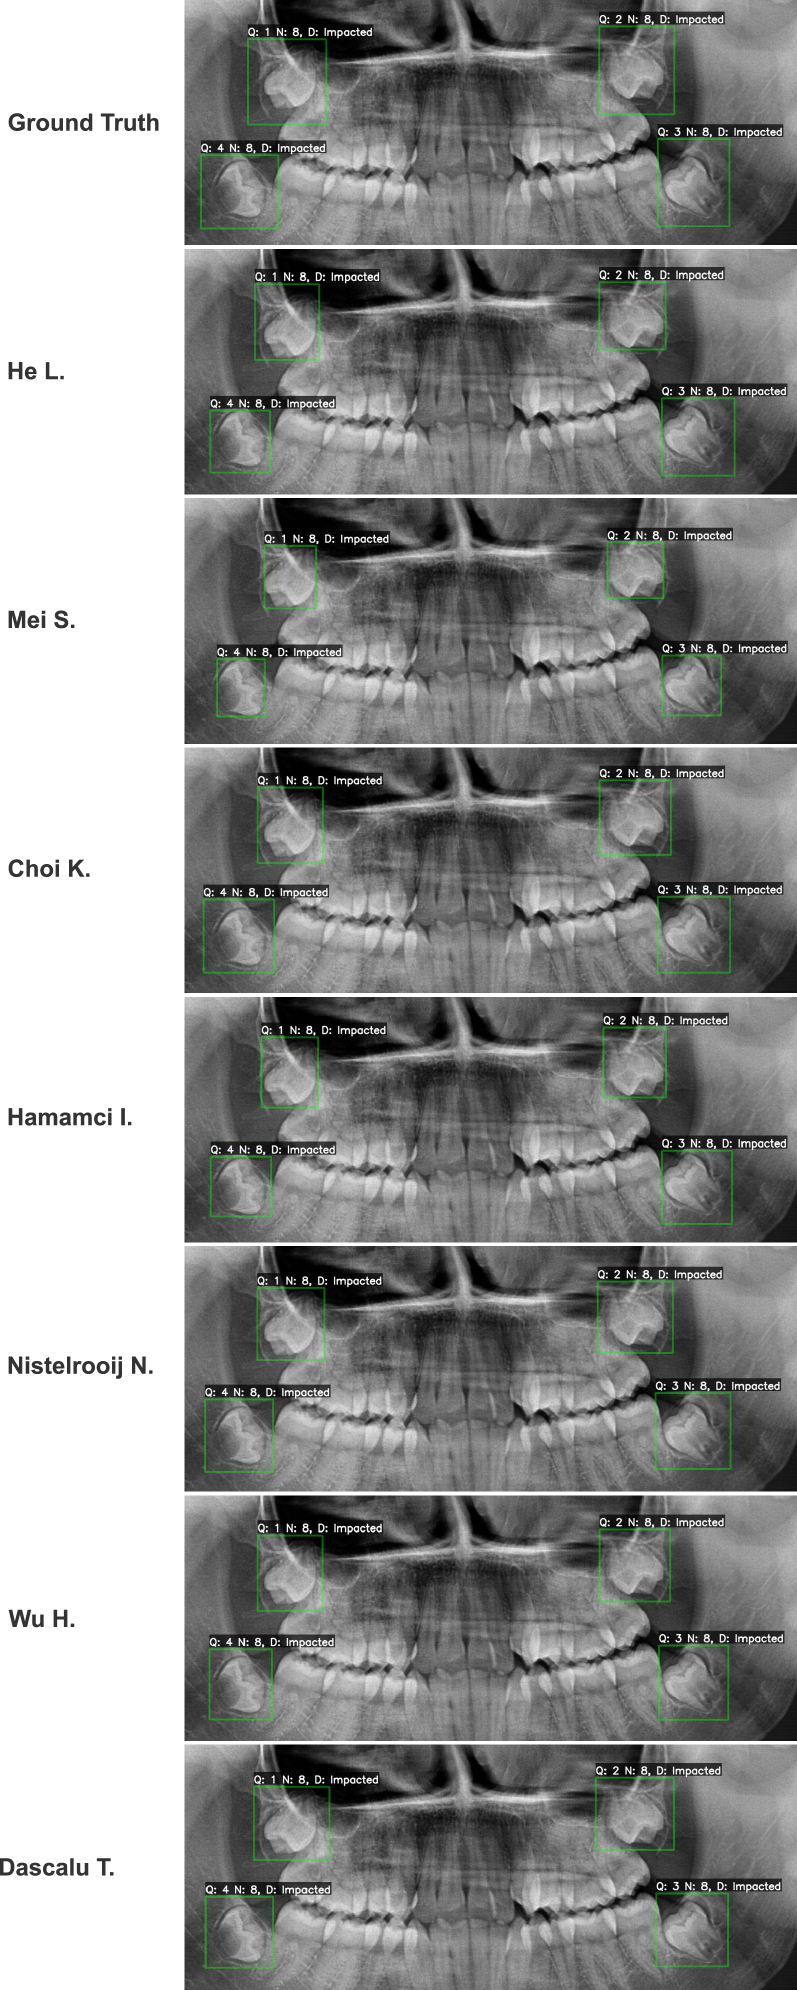

Refer to caption

Figure 5: Qualitative performance of submitted models on an unambiguous pathology class: Impacted third molars. This figure illustrates a common finding where models across the performance spectrum achieved success, from the top-ranked He L. to the lowest-ranked Dascalu T.

As illustrated in Fig. 5, the task of identifying impacted third molars, a pathology with clear anatomical displacement, was relatively straightforward for most algorithms. Even the lowest-ranked method was capable of correct identification in this scenario, producing a result comparable to the top performers. This success across the board suggests that the significant performance gaps observed in the overall metrics (Table 2) were not driven by these simple cases. Instead, the true challenge of the benchmark lay in detecting and classifying the more subtle pathologies, which served as the primary differentiator between the methods. In contrast, a hard periapical lesion case is given in Fig. 6.